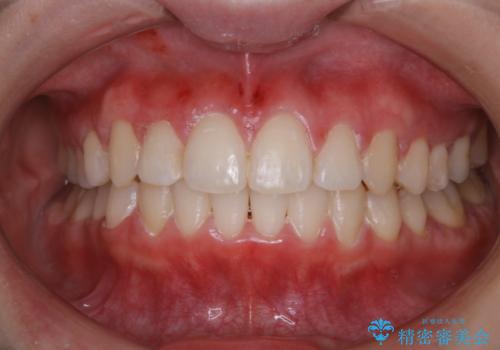

- マスクの着用により、以前より口臭が気になるとのことでした。しっかりと全体的なクリーニングを希望されたため、PMTC60分コースを行いました。

PMTCとはProfessinnal Mechanical Tooth Cleaning・専門器具による歯の機械的な清掃です。

バイオフィルム(細菌の塊)を破壊し、歯の表面をツルツルにすることでお口の中の細菌数を減らし歯周病のリスクが定着するのを防ぎます。更に、歯に新しい汚れがつきにくい状態になります。

バイオフィルムが除去されると、ご自身本来の歯の表面になります。PMTCをすることで口臭予防にもなり、定期的に行うことが大切です。